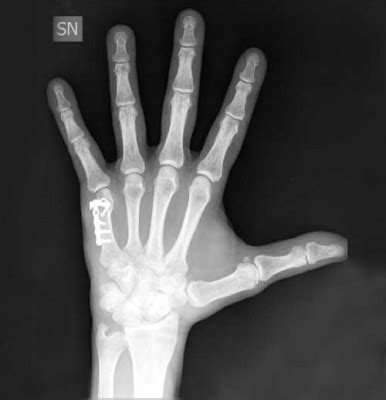

Qual è la frequenza della frattura al metacarpo? Anch'io,tra i vari altri danni,mi son rotto il v° metacarpo in bici,frattura riparata con una vite in titanio,peraltro messa male da un amico carissimo! Se trattata rapidamente, una frattura metacarpale.

Vengono qui illustrate le tecniche chirurgiche di ostesintesi per la frattura del metacarpo e le fratture multiple dei metacarpi. Nei radiogrammi eseguiti non evidenza di franche alterazioni a focolaio in atto. La frattura del pugile corrisponde alla frattura sottocapitale del quinto metacarpo. Rivalba, nel frontale con il tir vettura distrutta: Complicanze tardive delle fratture della mano. Tutore frattura 5 metacarpo in vendita on line a prezzi imbattibili su ausilium. Infine, in presenza di una frattura. Pagesbusinessesmedical & healthdoctororthopedistmerola ortopediavideosfrattura 5 metacarpo prima della vacanza.il mare è assicurato. Oggi inavvertitamente in casa, mentre chiudevo la finestra ho sbattuto la mano contro la finestra, niente di tremendo ma per un po' mi ha fatto male. Dopo diagnosi frattura testa v metacarpo mano dx (caduta accidentale), mi viene applicato apparecchio gessato con immobilizzazione delle 4 dita, con pollice separato e gomito mobile. Alla rimozione dopo 40 giorni,il paziente presenta rigidità a tutta la mano, in particolare al 4° e 5° dito. Cause e fattori di rischio. Prova a trovare tutore frattura 5 metacarpo in questa pagina, oppure utilizza il motore di ricerca: Il trattamento di una frattura del metacarpo dipende dalla gravità dell'infortunio. Anch'io,tra i vari altri danni,mi son rotto il v° metacarpo in bici,frattura riparata con una vite in titanio,peraltro messa male da un amico carissimo! Alla rimozione, la mano risultava oltremodo gonfia, di colorito un po' più scuro del normale, calda al tatto e. Deformità rotazionale dovuta a una frattura interessante la mano.